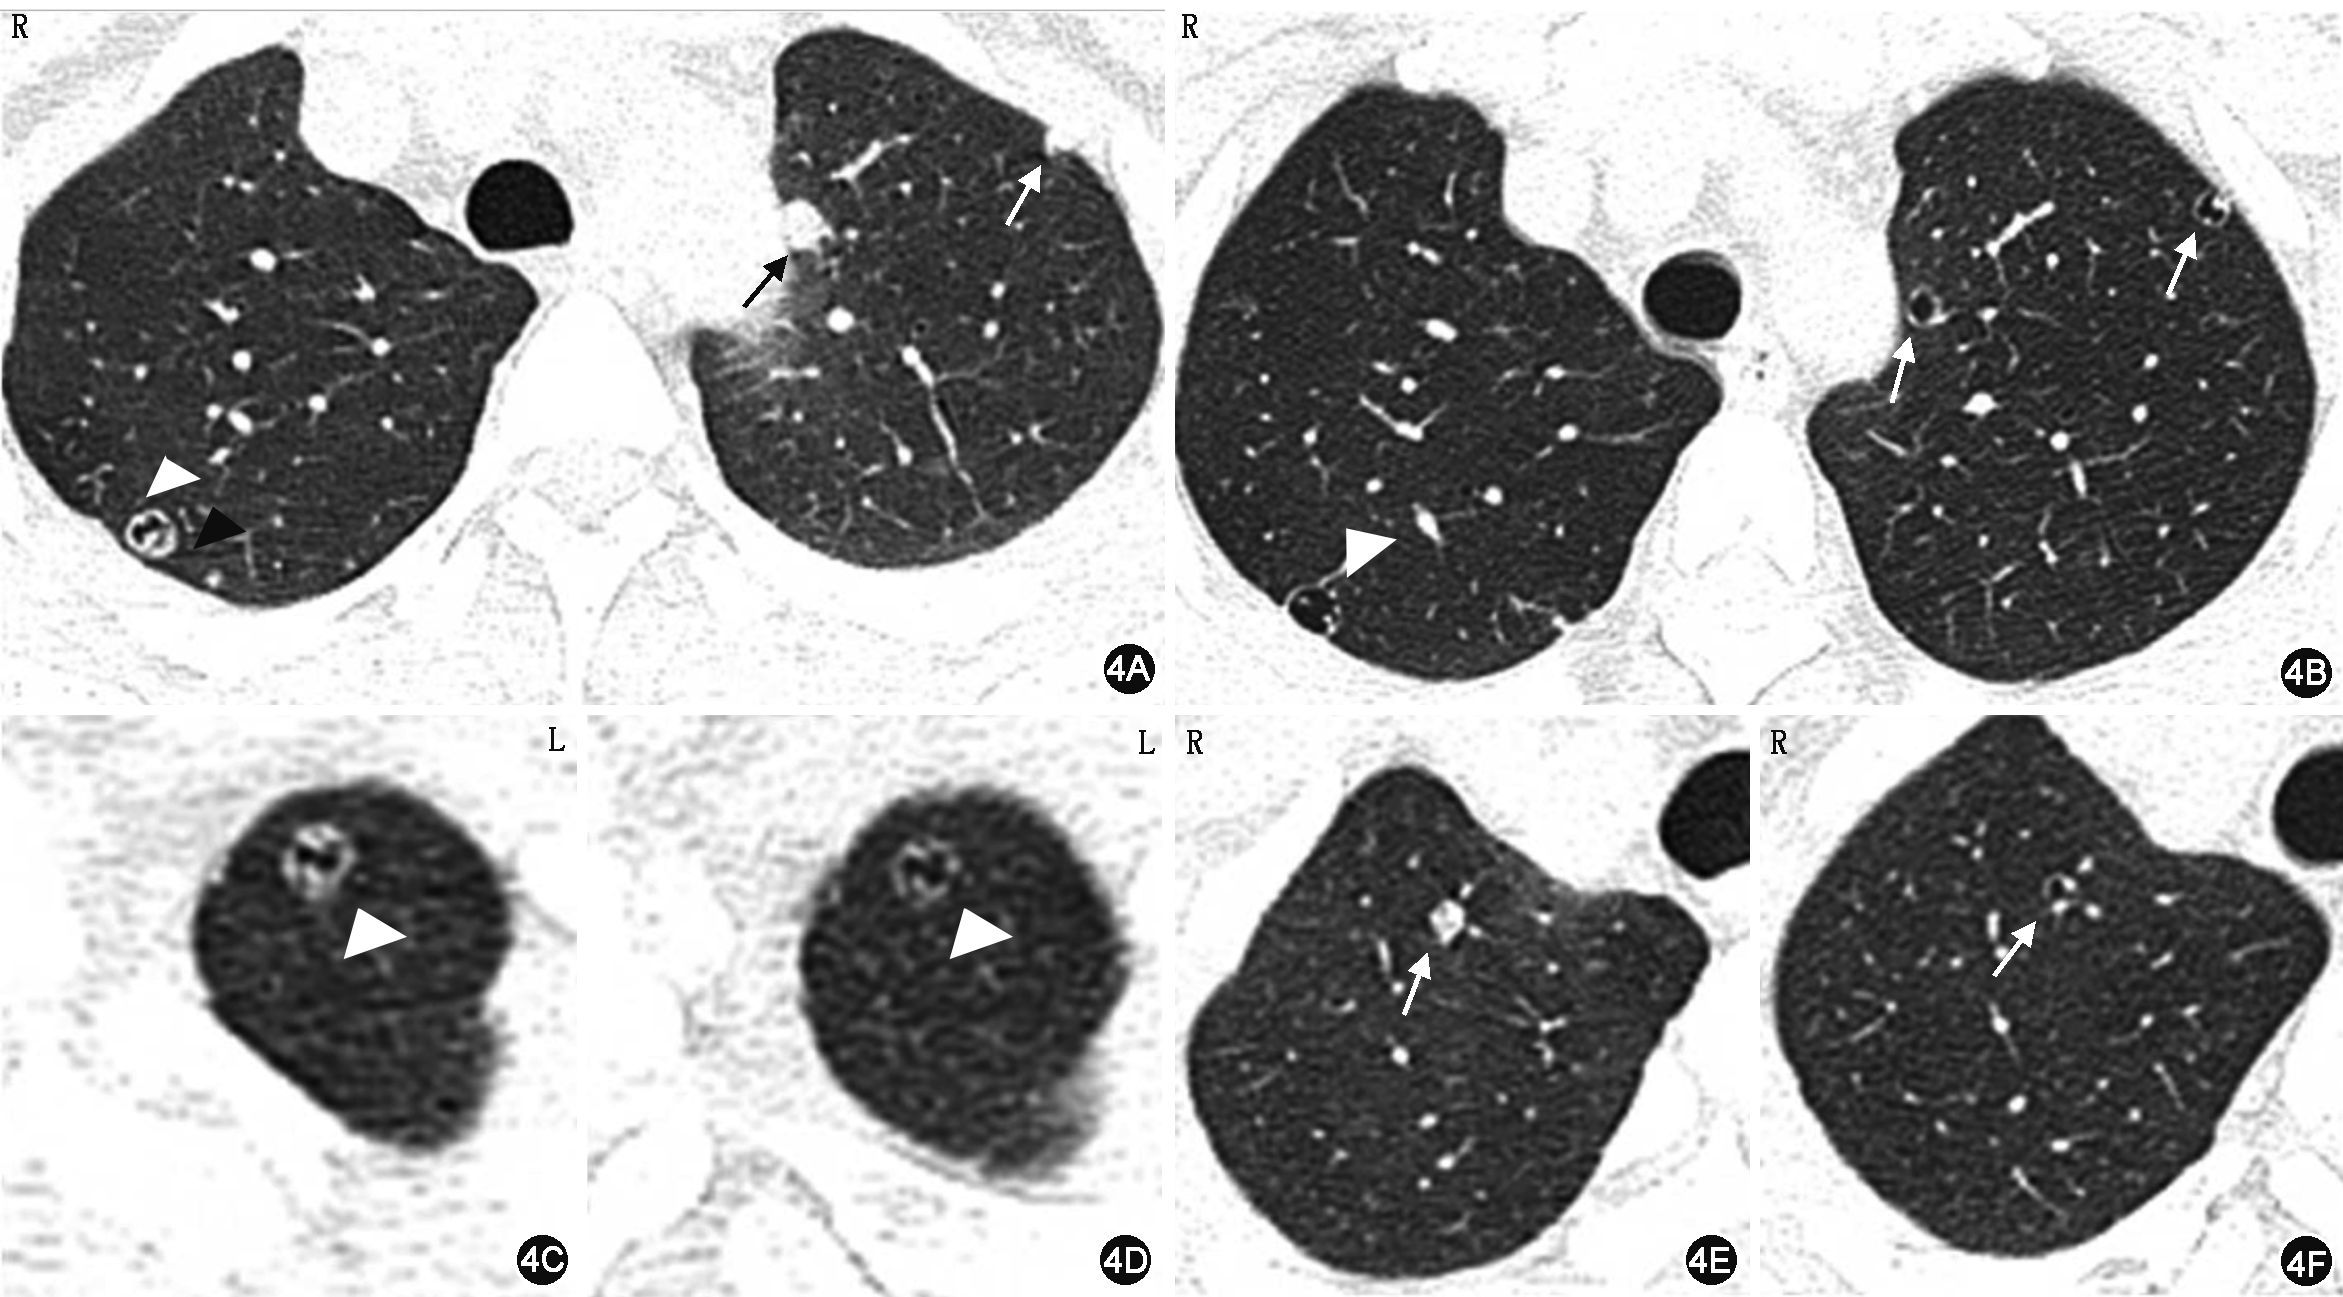

A~B:示右肺上叶囊腔样病灶的实性成分明显减少(白箭头),其后方1枚小结节(图4A黑箭头示)术后未见明确显示,左肺上叶2枚实性结节术后表现为囊腔样(白箭头);C~D:示左肺尖囊腔样病灶的壁术后明显变薄(白箭头);E~F:示右肺上叶实性结节术后呈囊腔样(白箭头)

术后患者恢复良好,3个月后复查胸部CT,与术前相比较,除左肺上叶舌段1枚实性结节及2枚囊腔样结节手术切除外,其余肺内结节中实性成分均不同程度减少:大部分实性结节见囊腔形成,部分实性结节体积明显缩小,而原囊腔型结节病灶的壁明显变薄,无新发结节。持续随访中(图4)。